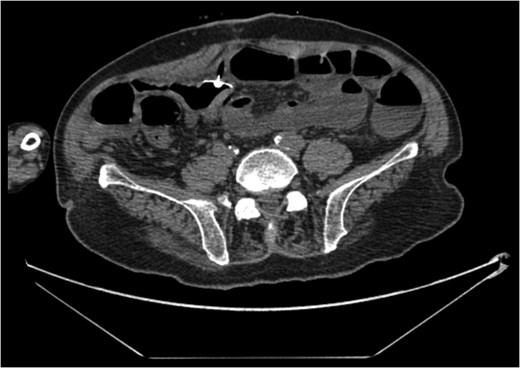

A 68-year-old male nursing home resident presented following dislodgement of a percutaneous endoscopic colostomy (PEC) tube originally sited to prevent recurrent sigmoid volvulus. Computed tomography demonstrated tube migration into the lumen of the recto-sigmoid junction, where it remained for 12 days before passing spontaneously. During this period, the patient remained asymptomatic; the residual colocutaneous fistula functioned as a decompressive valve. Originally, the patient was due to be discharged with early flexible sigmoidoscopy follow-up. However, complex social issues delayed discharge. During his admission, a second PEC tube was successfully inserted next to the previous colostomy site without complication. This is an unusual case and no similar episodes of asymptomatic PEC migration have been reported. We demonstrate that such cases may be offered an appropriate trial of conservative management. Here, we describe our experience and critically appraise the literature.

The patient remained asymptomatic with a soft, non-tender abdomen. The only abnormal clinical finding was the absence of a PEC tube from a patent periumbilical colostomy site.

The patient remained well and the PEC tube passed spontaneously on Day 12, during a bowel motion.

Tube migration leading to perforation and frank peritonitis has been described elsewhere [10]. However, there are no cases of asymptomatic dislodged PEC tubes. Following discussion with gastroenterology and colorectal surgery, the decision was made to let the PEC pass spontaneously or remove it during early follow-up flexible sigmoidoscopy. The PEC tube was naturally expelled on Day 12 without complication.